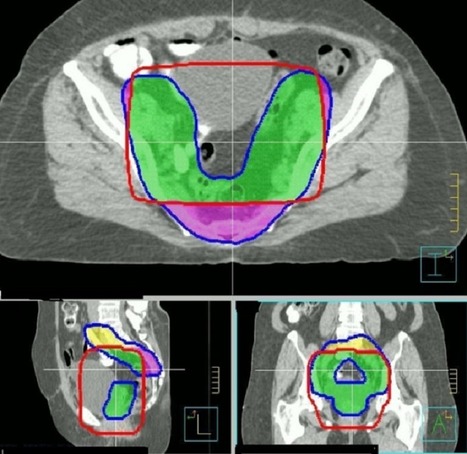

Involvement Of Plasma Copper, zinc And Cadmium In Human ...

Keywords: Cervical cancer, copper, zinc, cadmium, radiation, uterus. Introduction: Cancer of the cervix is the most common carcinoma carcinoma of uterine cervix and their status after radiation therapy. Subjects and methods: The investigations were conducted in ... Read Full Source